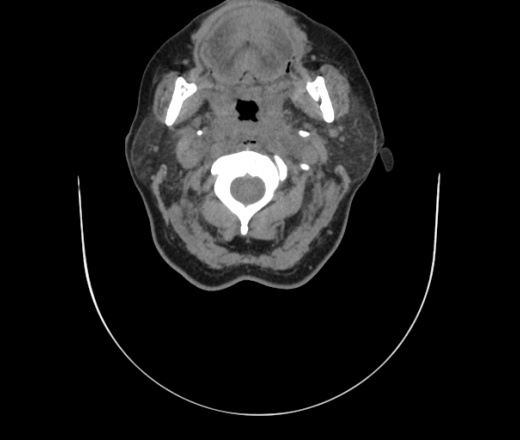

Женщина поступила в х/о спустя 4 дня после того как при употреблении карася подавилась костью.

Наличие газа в средостении на протяжении тел С2-С6 (медиастинальна эмфизема); рыбная кость на уровне тела С6.

При всем уважении, но говорить о медиастинальной эмфиземе, оценивая мягкие ткани шеи, как-то слишком резко. На мой взгляд, это ретрофарингеальное пространство.

Согласен с Вами; конечно, наличие газа в клетчатке ретрофарингеального пространства (затмение с опечаткой..). К сожалению, процесс "продвигается" к медиастиниту. Но почему никто, не отмечает наличие рыб. кости; или это для Всех очевидно?

Кость то мы сразу выявили, размеры где то 17*2мм, но ее так и не получается найти в этой каше